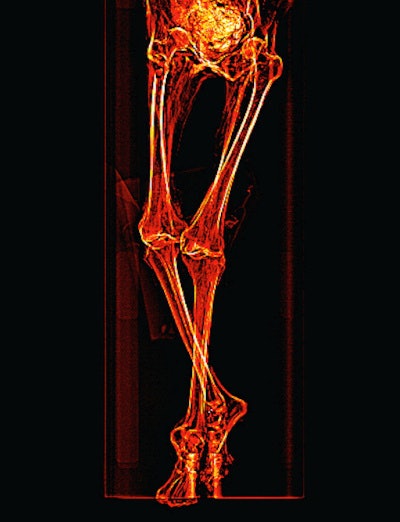

Saleem obtained maximum length measurements of the major long bones. The right femur measured 402 mm, left femur 401 mm, right tibia 338 mm, left tibia 338 mm, right fibula 338 mm, and left fibula 339 mm. Because of the oblique posture of the mummy, it was impossible to obtain a vertex-to-heel measurement. The stature was estimated to be about 151 cm ± 2.5 cm based from the femur length using regression equation derived for ancient female Egyptians.

Scout CT scan shows the mummy's legs are partly flexed and crossing at the ankles, with the left leg above the right.She noted that definite atherosclerotic changes are visible as high-density areas of calcification within the walls of identifiable arteries: right and left carotid bulbs, right and left coronary arteries, abdominal aorta, superior mesenteric artery, coeliac artery, bilateral iliac, femoral and peripheral leg arteries. Also evident was mild lateral curvature of the dorsal spine with its convexity to the left (scoliosis); no structural abnormalities of the spine or anomalous vertebrae could be seen.